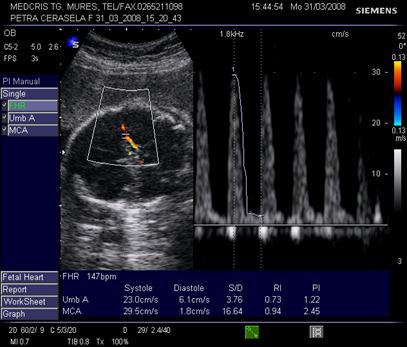

Doppler pe artera ombilicala

Daca fasciculul Doppler ("poarta") este bine centrat, sunetul este optim si spectrul este caracteristic pentru artera din cordonul ombilical. Linia de baza trebuie sa separe fluxul arterial de cel venos.

Derularea benzii cu spectrul Doppler va "curge" pana cand exista parametrii de calitate:

sunet caracteristic

minim 5 cicli consecutivi, identici, bine conturati, deasupra liniei de baza

fluxul venos continuu este sub linia de baza

Fig. nr. 320. Artera ombilicala, stanga indicele de pulsatilitate , dreapta indicele de rezistenta, valorile normale intre a 5 a si a 95 a percentila, scad cu cresterea fetala. ( adaptat dupa Merz [16] )

Fig. nr.321. Spectru Doppler normal pe artera ombilicala

Primele ecografii Doppler in sarcina cu antecedente patologice incep la 22 - 24 saptamani si se repeta la 28 - 32 sapt., sau chiar mai repede in cazul depistarii unor unde anormale.